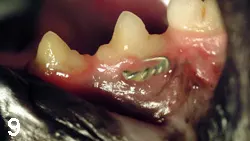

The ResultsAfter monitored recovery, the animal was sent home and the owner was instructed to feed the cat soft food and to flush the splints daily with diluted chlorhexidine solution. On physical presentation at the planned 8-week recheck for splint and wire removal, the gingiva was a normal pink and had grown around the cerclage wire (Figure 9). The jaws were aligned, and there was no evidence of dental malocclusion. The intraoral splints had fallen off by themselves. The radiographs indicated normal fracture healing (Figure 10). The caudal ramus wire was removed.